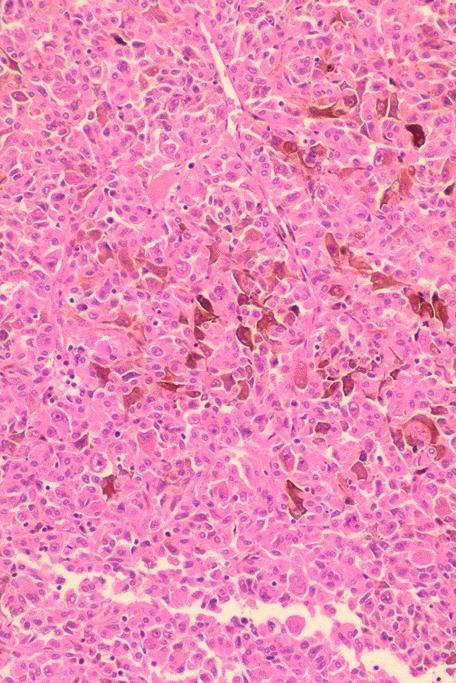

Microscopic (histologic) description

- Wide variety of morphology, can mimic any other thyroid malignancy

- Round, plasmacytoid, polygonal or spindle cells in nests, cords or follicles; often mixtures of these cells

- Round nuclei with finely stippled to coarsely clumped chromatin and indistinct nucleoli, occasional nuclear pseudoinclusion

- Eosinophilic to amphophilic granular cytoplasm due to secretory granules

- Generally low mitotic figures

- Stroma has amyloid deposits from calcitonin, prominent vascularity with glomeruloid configuration or long cords of vessels (Am J Surg Pathol 1995;19:642), coarse calcifications, occasional psammoma-like bodies

- Often angiolymphatic invasion

- Occasionally marked neutrophilic infiltrate, oncocytic tumor cells, papillary patterns

Microscopic (histologic) images

Contributed by Shuanzeng Wei, M.D., Ph.D., Joseph Christopher Castillo, M.D. and Mark R. Wick, M.D.

AFIP images

Images hosted on other servers: